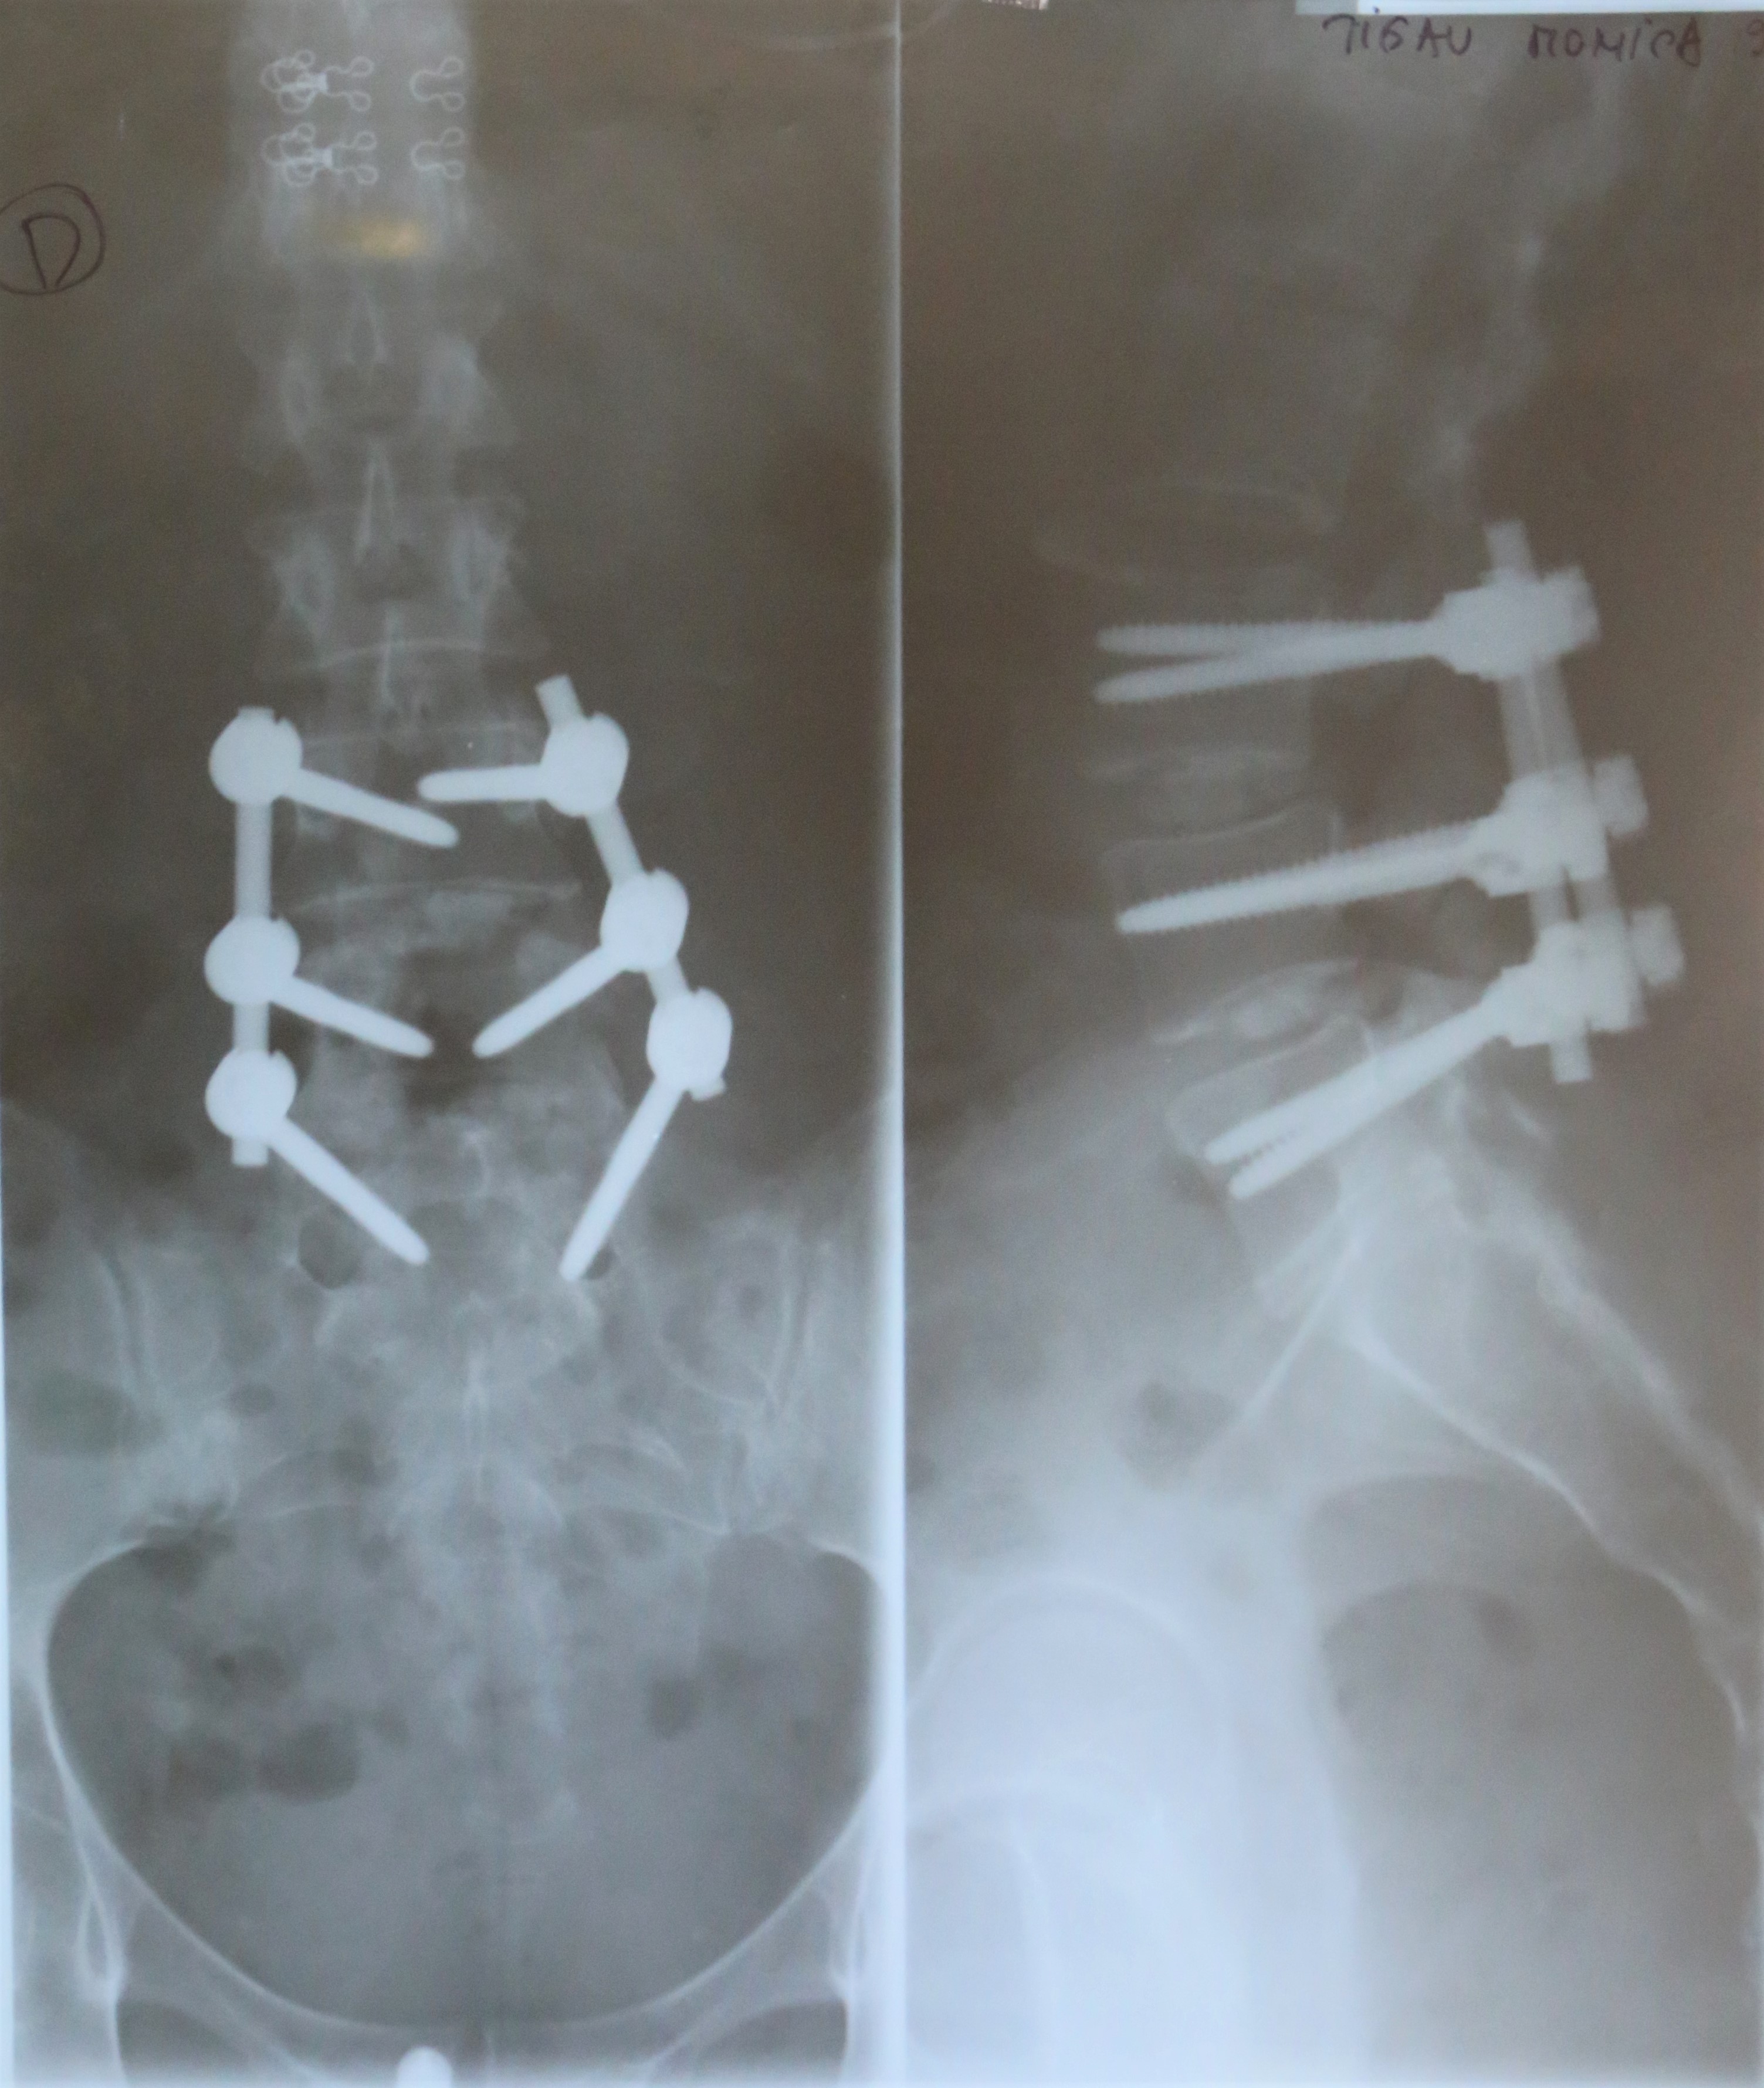

SPONDILOLISTEZA L4-L5